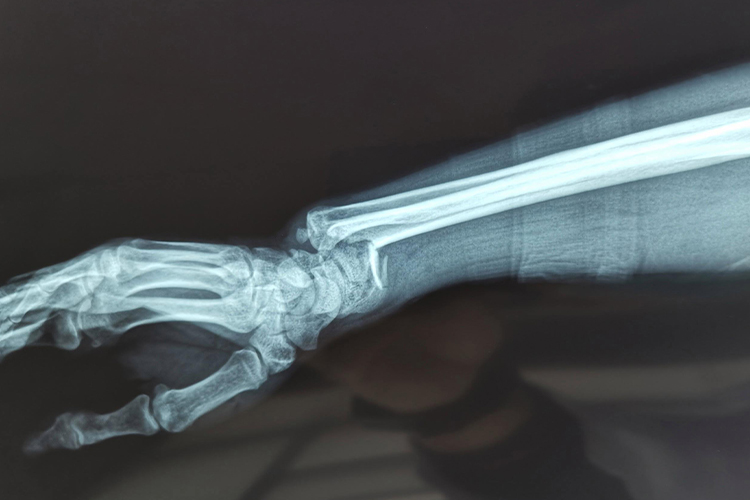

银叉样畸形是由于桡骨远端骨折引起,多见于Colles骨折,通常患者骨折后局部疼痛、肿胀、可出现典型畸形姿势,即侧面看呈“银叉样”畸形,正面看呈“枪刺样”畸形。局部压痛明显,腕关节活动障碍。X线拍片可见骨折远端向桡、背侧移位,近端向掌侧移位,可同时伴有下尺桡关节脱位及尺骨茎突骨折。

银叉样畸形多为间接暴力引起,因跌倒时手部着地,且多为腕关节处于背伸位、手掌着地、前臂旋前时受伤,暴力向上传导,从而发生桡骨远端骨折。